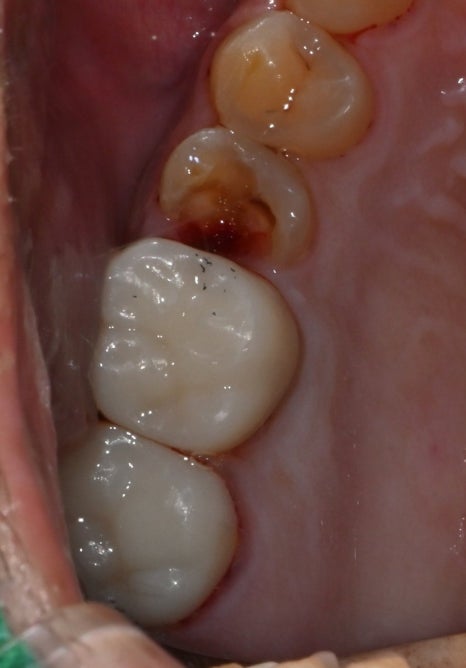

예를 들어 신경치료 사례예시를 보여드립니다.

초진내원당시

오른쪽 이가 깨졌는데 시리고 아파요

엑스레이를 확인해보니 충치가 너무 심해 치아가

깨진 상태로 오셨어요.

<치료 전 / 치료 후>